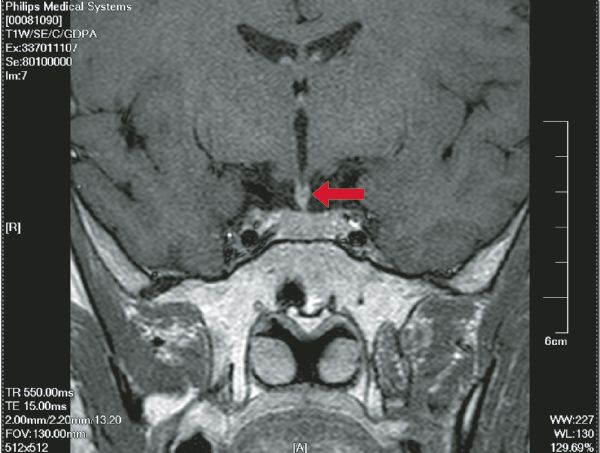

Xiaoyan Chen, Xiaochun Huang, Yuan Qiu, Hanzhang Chen, Yingyu Fu, Xinchun Li

Langerhans cell histiocytosis (LCH) is an idiopathic group of reactive proliferative diseases linked to aberrant immunity, pathologically characterized by clonal proliferation of Langerhans cells. LCH rarely involves the thymus. We report a case of thymic LCH with diabetes insipidus as the first presentation, without evidence of myasthenia gravis and without evidenced involvement of the skin, liver, spleen, bones, lungs and superficial lymph nodes. This present case may have important clinical implications. In screening for LCH lesions, attention should be attached to rarely involved sites in addition to commonly involved organs. Follow-up and imageological examination are very important to a final diagnosis.